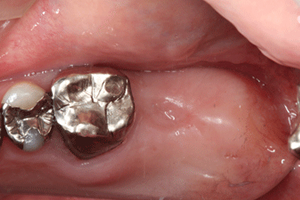

ソケットリフトによる奥歯のインプラント症例

右上に1本のインプラントをした症例です。患者様自身、虫歯で奥歯を失ったため、食生活や、他の歯への負担、歯の移動などを不安なされていたため、インプラントの選択を行なわれました。

術後の写真は、インプラント植立を行なった後6ヶ月後に被せものをはめた状態です。